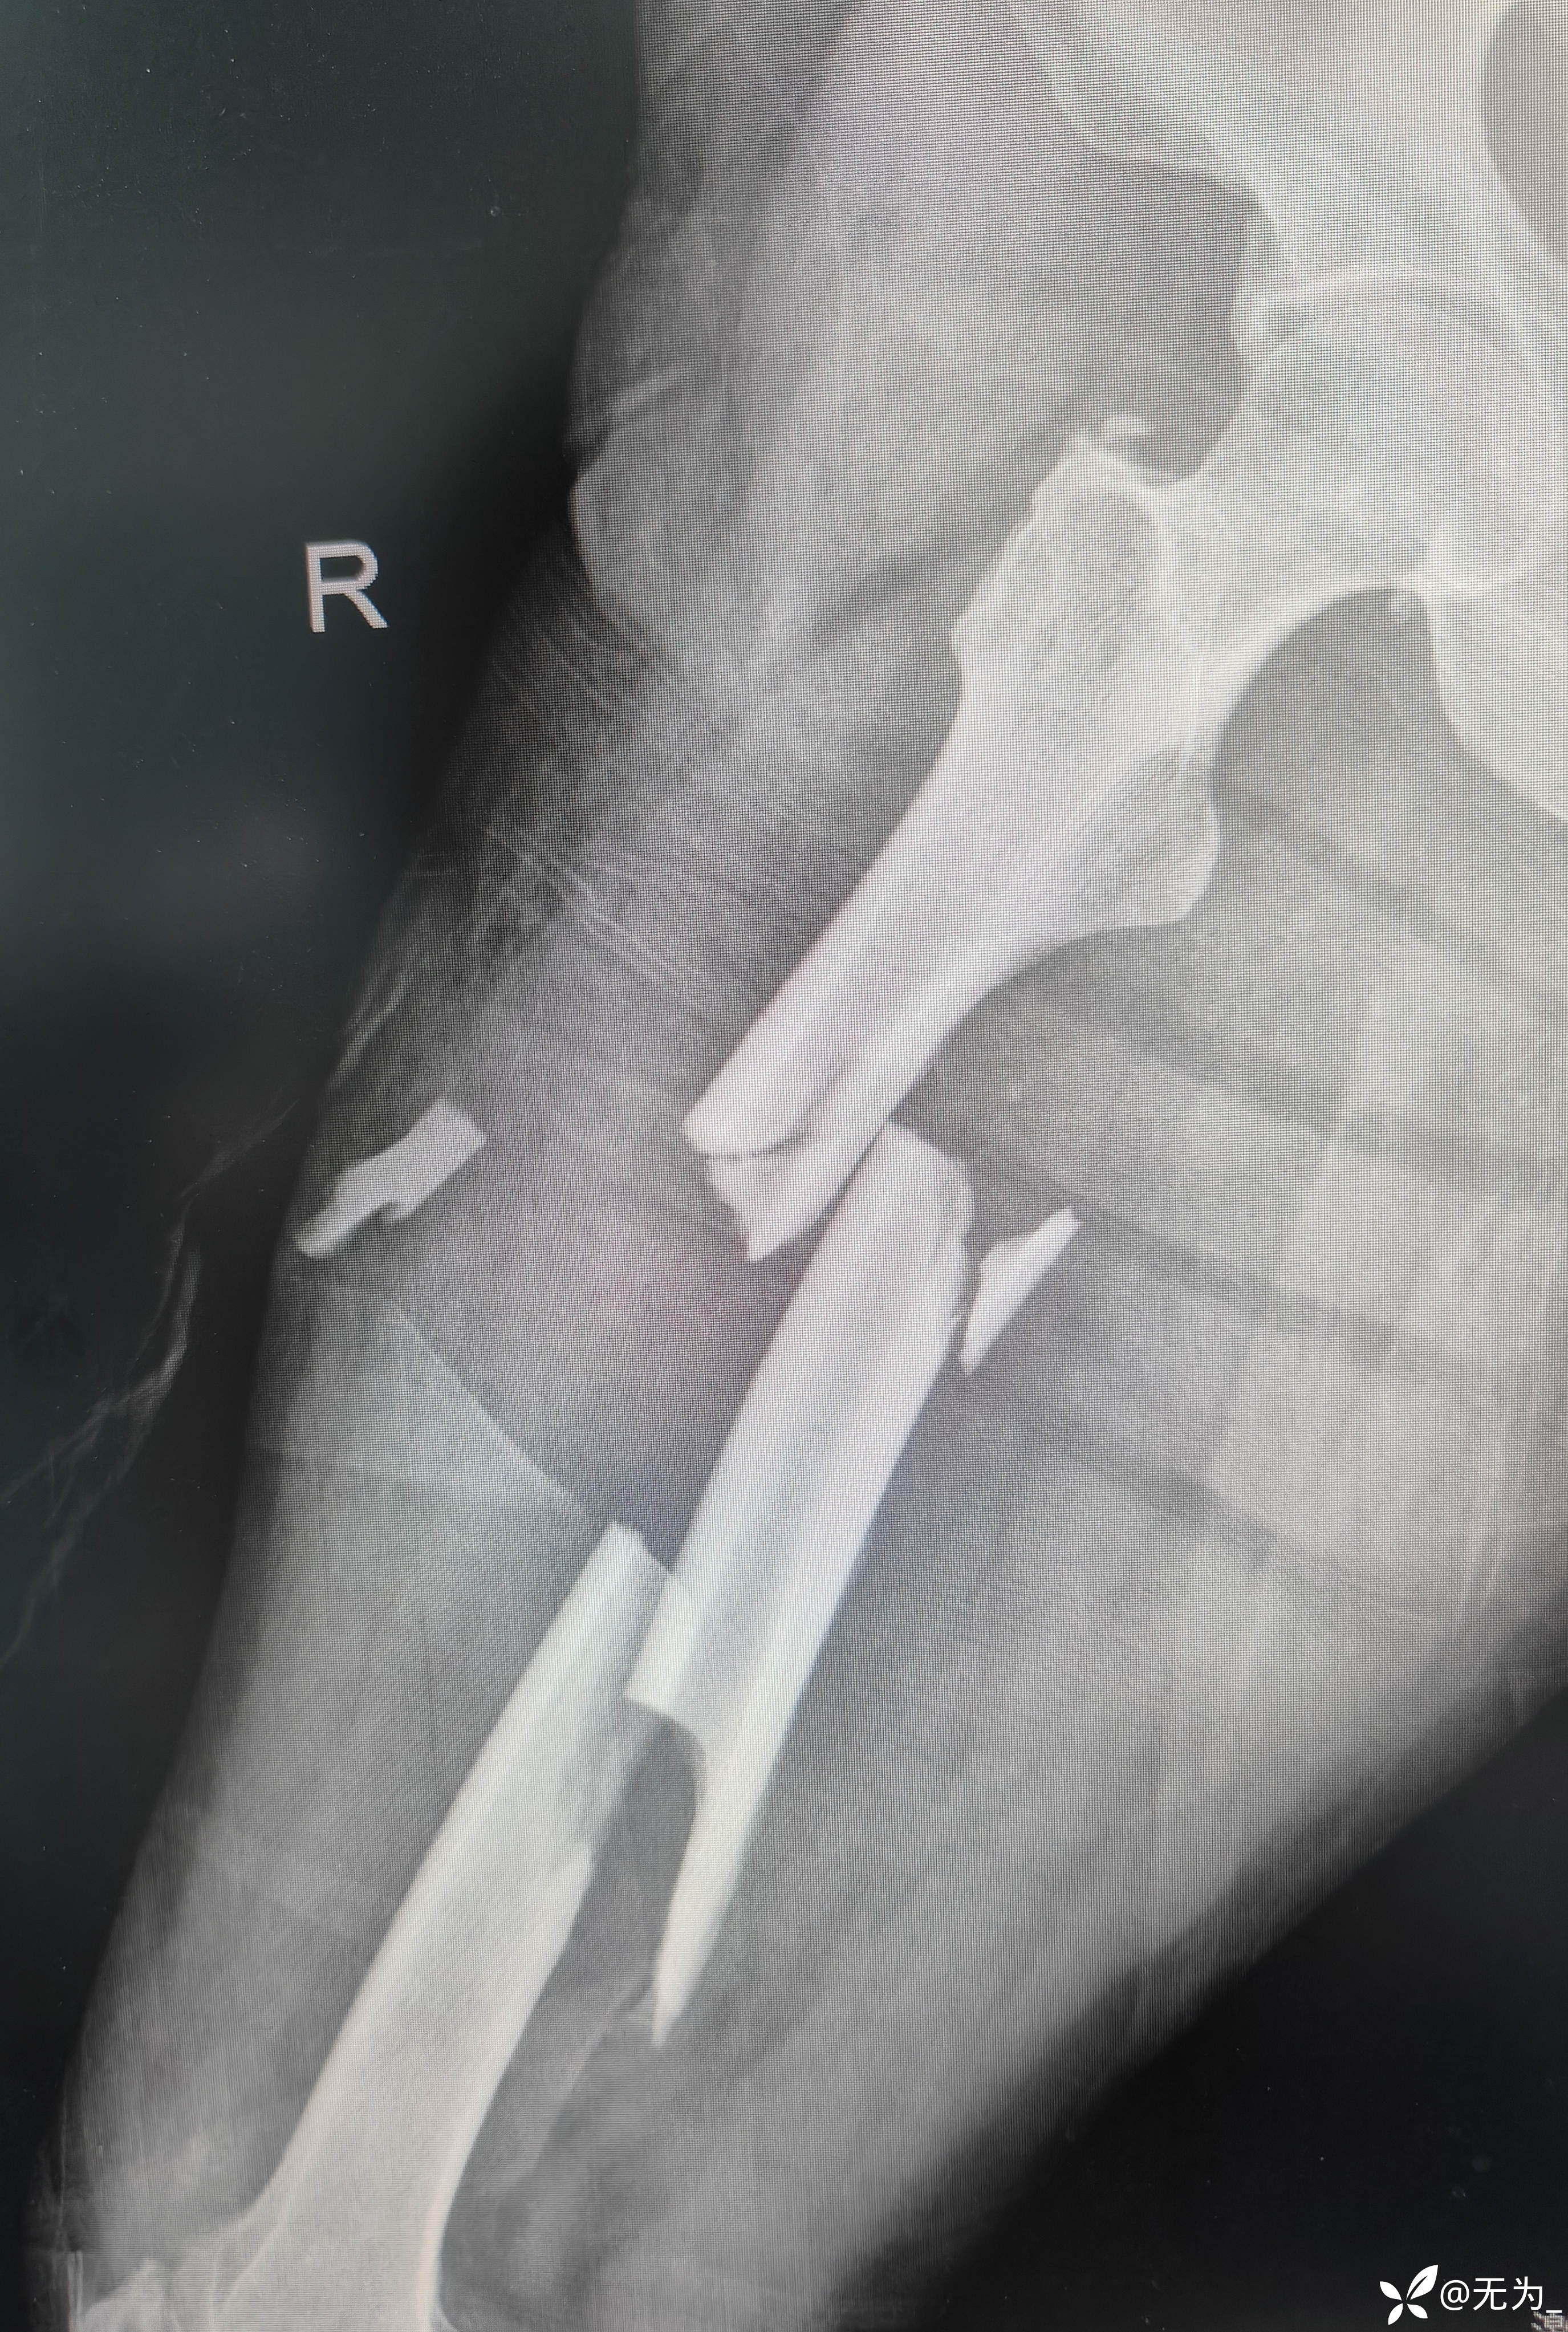

【患者信息】:患者55岁,车祸伤致全身多发骨折外院转入,生命体征不稳。

查体:右大腿中段前外侧两公分开放伤口,渗血,可处理游离骨块,大腿畸形、肿胀,足背动脉搏动可查。

补液、输血后行头外伤缝合、大腿外架临时固定,转icu,病情逐渐稳定,3周后行右股骨外架拆除,复位内固定。